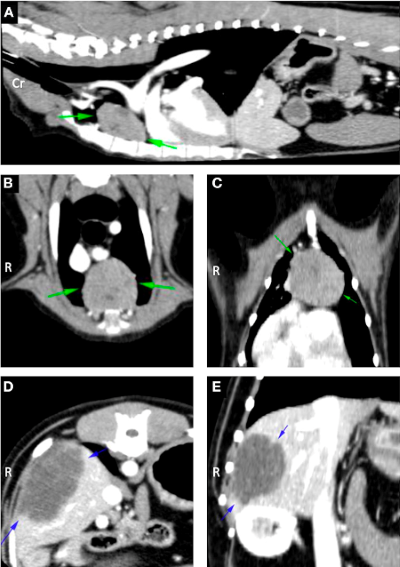

Investigations revealed myasthenia gravis, a severe immune mediate disease that interferes with neurotransmission necessary for muscle contraction and strength. Trevor was also found to have a cranial mediastinal mass which is concurrently reported in approximately 3.4-11% of dogs with this condition, as well as a hepatic mass.

Trevor’s weakness was addressed in the first instance by the neurology team with Pyridostigmine Bromide, an anticholinesterase medication that improves neurotransmission, thereby alleviating the muscle weakness and fatigability. Once his condition had stabilised, the soft tissue surgery team was successfully able to surgically resect both masses.